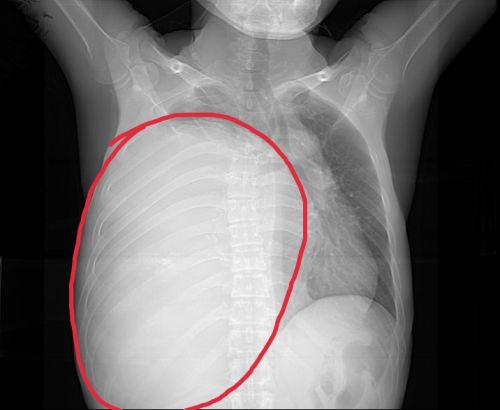

术前胸片提示,右侧胸腔内有一个巨大混杂密度包块(红圈内)。

患者胸腔内的巨大畸胎瘤约40×25cm大小。

切除的肿瘤重达5049g。

长沙中年男子胸痛、胸闷、气促近两个月,“罪魁祸首”竟然是胸腔内长出的“大冬瓜”——一个重达5kg的巨大畸胎瘤。

开胸探查发现,徐先生右侧胸腔内的肿块质地坚硬,呈长椭圆形,像个“大冬瓜”,向上抵达胸腔顶部,向下推挤膈肌至脐水平,直径约40cm、横径约25cm。术中,主刀医师依次切除胸腔内肿块各分叶后,发现仍有少部分瘤体粘连在左心房底部,只得切除少许心房壁。

手术耗时约6小时,患者胸腔内肿块被全部取出,切下的巨大畸胎瘤重约5kg。术后,患者恢复良好,于813日痊愈出院。